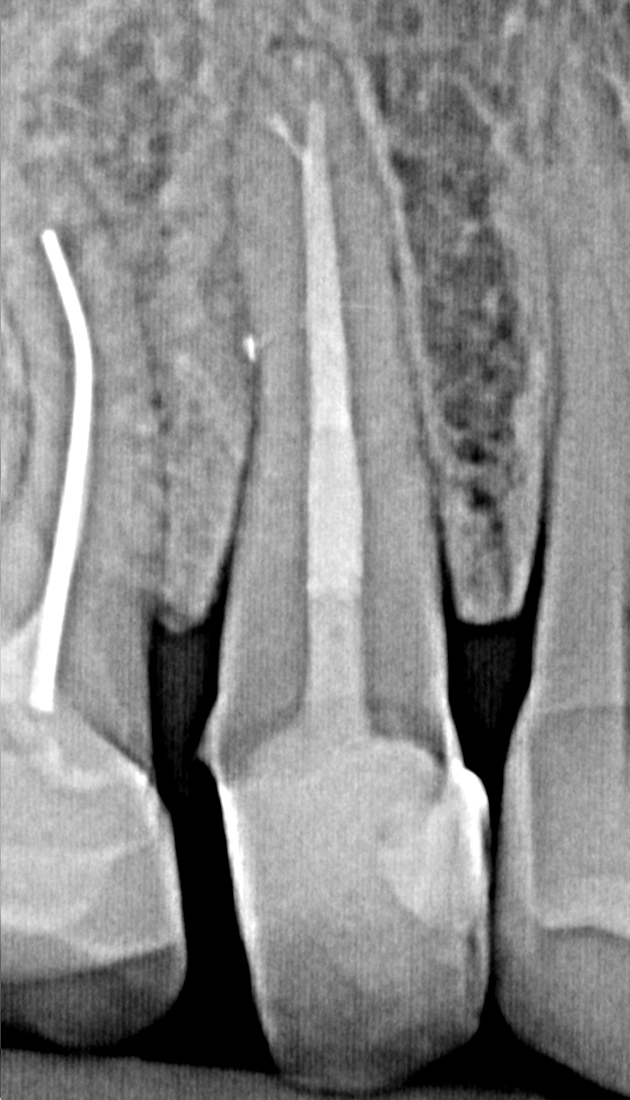

In bestimmten Fällen kann es jedoch auch ohne ausgeprägte Schmerzsymptomatik zum Absterben des Zahnnervs in Folge einer Entzündung kommen (Pulpennekrose). Bakterien können nun das abgestorbene Gewebe besiedeln und über die Wurzelspitze hinaus den umliegenden Knochen entzünden (apikale Parodontitis). Eine solche Entzündung kann akut mit starken Beschwerden wie Schwellung, Fieber und Schmerzen einhergehen. In vielen Fällen kommt es jedoch zu einem chronischen Verlauf, der langfristig zum Knochenabbau im Bereich der Wurzelspitze führt. Eine solche chronische Entzündung kann über Jahre unbemerkt verlaufen, jedoch unter bestimmten Voraussetzungen auch wieder in ein akutes Stadium übergehen.

Das Zahnmark bildet ein komplexes Hohlraumsystem im Inneren des Zahns. Trotz großer Sorgfalt kann in manchen Fällen nicht das gesamte Wurzelkanalsystem gereinigt werden. Durch nicht ausreichend gereinigte Wurzelkanalabschnitte oder nicht aufgefundene Kanäle kann es zu einer erneuten bakteriellen Besiedlung und Infektion der Wurzelkanäle kommen.

Eine neue oder fortbestehende Infektion des Wurzelkanalsystems führt zu einer akuten oder chronischen Infektion des umliegenden Knochens. Mit modernster Technik und dem Einsatz des Dentalmikroskops lassen sich solche Zähne erneut behandeln. Dabei muss die alte Wurzelfüllung entfernt werden, nicht gereinigte Kanäle und Kanalabschnitte gesäubert und schlussendlich das gesamte Kanalsystem desinfiziert werden. So lassen sich langfristige Erfolgsquoten von bis zu 95% erreichen.

Das Mikroskop ist das wichtigste Hilfsmittel des endodontisch tätigen Zahnarztes. Mit einer bis zu 24-fachen Vergrößerung und direkter Ausleuchtung des OP Gebiets können kleinste Strukturen innerhalb des Zahns, wie verlegte Kanäle, Seiten- und Nebenkanäle und tiefe Aufzweigungen von Kanälen oder Mineralablagerungen im Inneren des Zahns dargestellt werden. Ebenfalls werden bestimmte Behandlungen wie die Entfernung von frakturieren Wurzelkanalinstrumenten oder die Therapie anderer Komplikationen erst durch den Einsatz des Dentalmikroskops ermöglicht.